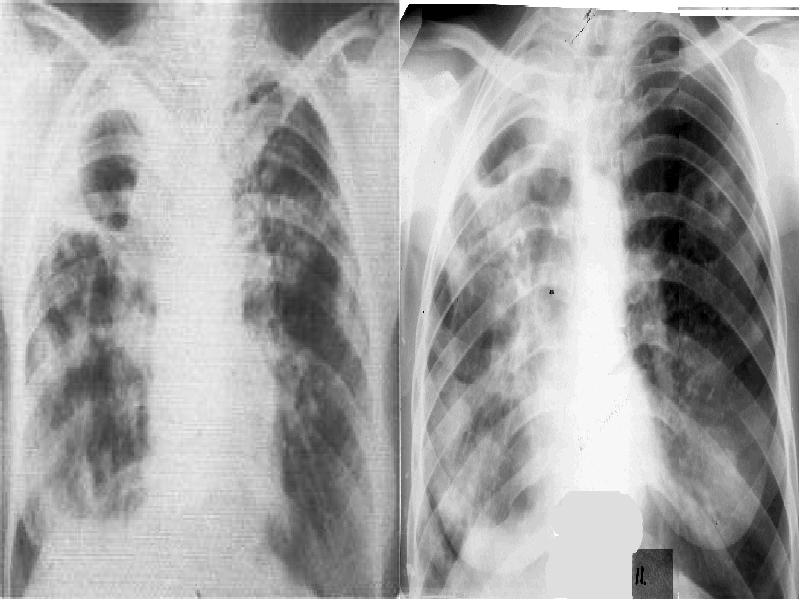

- 5. Рентгенология Рентгенограммада фиброзбен өкпенің семуі көрінеді, ескі фиброзды коверна (бір немесе

- 7. Рентгенологиялық көрінісі Жаңа пайда болған эластикалық каверналар көбіне өзгермеген өкпе тінінде